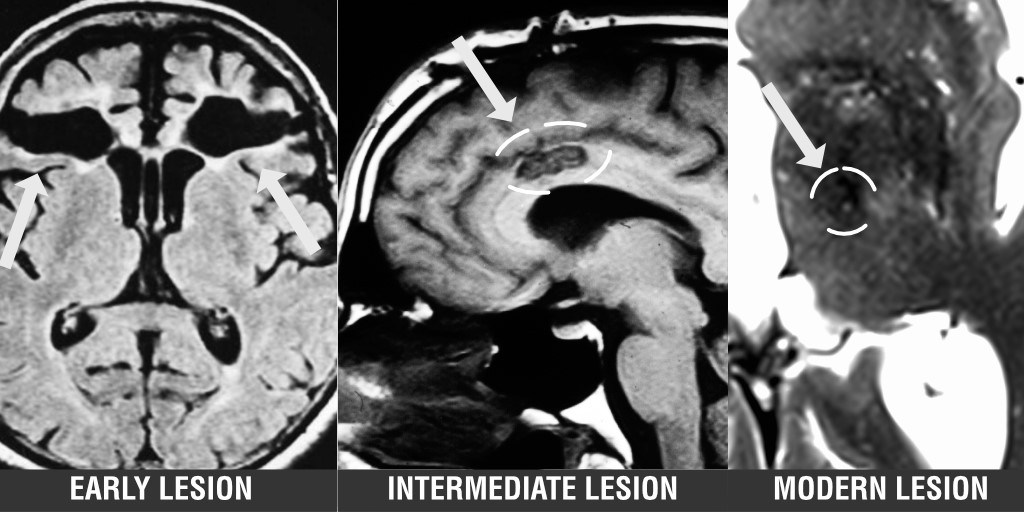

Historically, lesions were fundamental to localizing and treating neurological symptoms, but their use decreased over time. Joutsa et al. argue that improvements in technology mean that lesions may be making a comeback in the treatment of brain disease. bit.ly/3odNVMz